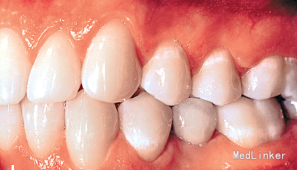

15岁女孩,牙列不齐

左下第二乳磨牙滞留,上下牙列轻度拥挤不齐.全景示左下第二乳磨牙无相应的恒牙,先天缺失35牙

诊断:35牙缺失,牙列不齐 治疗:排齐整平上下牙列,对滞留的乳磨牙处理如下:因乳磨牙宽大,较正常前磨牙近远中径大很多,正畸治疗过程中逐次给乳磨牙减径后树脂修复参与正畸治疗,使减径树脂修复后的乳磨牙宽度为以后修复的前磨牙宽度一致。减径后的间隙留作牙列内其他牙齿的排齐。

2年正畸治疗结束后,乳磨牙仍在。一年以后,患者18岁成年,拔除乳磨牙,植入植体,半年后套冠,效果很好,患者满意。有些先天缺失第二前磨牙的患者,若第二乳磨牙比较健康,可以减径后树脂修复参与正畸治疗,这样有保存骨量,维持牙弓间隙,保持与对合牙功能接触以免对合牙伸长的作用。骨量的保存利于植体的植入。